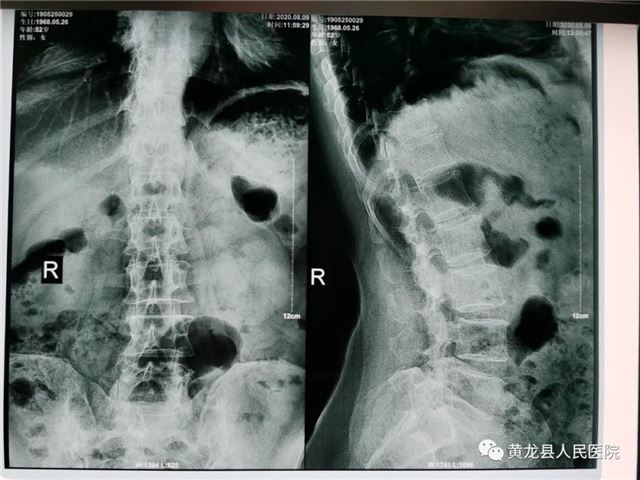

张某,女,52岁,近1月来,出现腰部疼痛,反复发作,并向左侧下肢放射,劳累后加重,休息后减轻,无法正常行走,严重影响生活质量,在家人陪同下来到黄龙县人民医院外科就诊。恰逢唐都医院骨科帮扶支援专家高全有副主任医师门诊坐诊,首诊详细了解患者病史,经仔细查体,结合影像学检查,最终诊断为:腰椎间盘突出症(L5-S1)。

术前腰椎正侧位